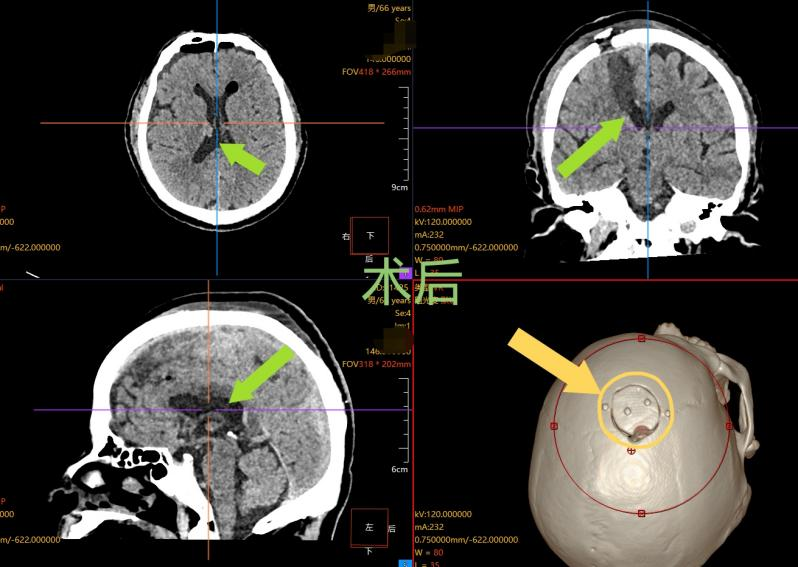

5.术后恢复超预期:微创技术带来快速康复

整场手术过程顺利,术后复查 CT 显示,张先生颅内的血肿已被满意清除,受压的脑组织得到有效减压。更令人振奋的是,这场高难度手术仅在患者头部留下长约 4 厘米的微小切口,骨瓣不足 3 厘米 —— 相比传统开颅手术的切口,创伤被降至最低。

得益于微创手术巨大优势,张先生术后恢复速度远超预期:头痛、呕吐等症状很快消失,神志转清,神经功能也得到最大程度保留。目前,张先生已能自主步行出院,家属对治疗效果给予高度认可。